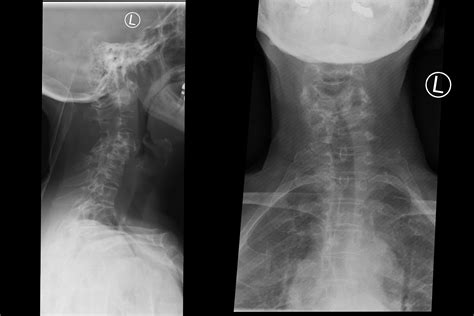

To determine if your pain is caused by arthritis in back, a physician will typically perform a physical examination and review your medical history. They will check your posture, range of motion, and nerve function. To confirm the diagnosis and rule out other conditions, they may order imaging studies:

Imaging Test Purpose

X-ray To view bone spurs, narrowing of joint space, and general bone structure.